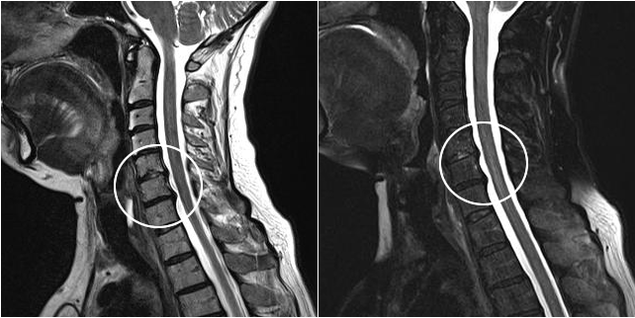

Modern diagnostic methods include magnetic resonance imaging and computed tomography, which make it possible to more accurately examine the processes of destruction of cartilage and bone tissue.Furthermore, using this technique it is convenient to diagnose hernias and other soft tissue defects close to the origin of the disease.